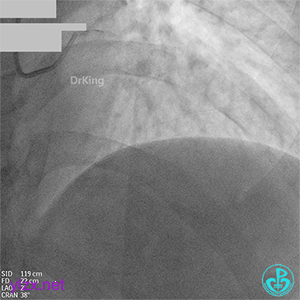

06 8天后复查冠脉造影

RCA粗大近中段瘤样扩张明显,中段血栓影消失,左室后支显影,后降支近段可见造影剂滞留, TIMI血流3-级。

08 1个月后复查

RCA粗大全程瘤样扩张明显,自近段闭塞,TIMI血流0级;可见自身桥侧支逆供RCA远段。

LM未见明显狭窄,LAD开口至近段明显瘤样扩张,自近段闭塞,TIMI血流0级,D1瘤样扩张,TIMI血流2级;可见D1逆供LAD中远段及RCA中远段。

LCX发育小,内膜不光滑,TIMI血流3-级,逆供RCA中远段。